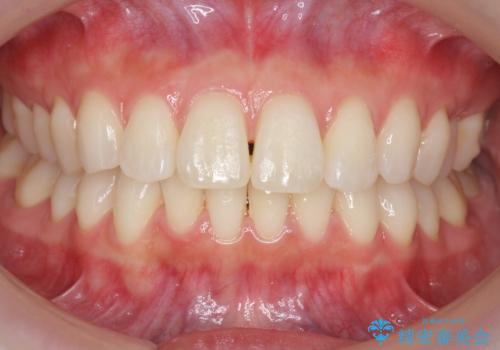

昔ワイヤー矯正をして後戻りした 軽度のがたつき モニター矯正

- 矯正治療後の後戻りを主訴に来院。

特に下の前歯のがたつきを気にされていました。

マウスピース矯正で再矯正を行いました。